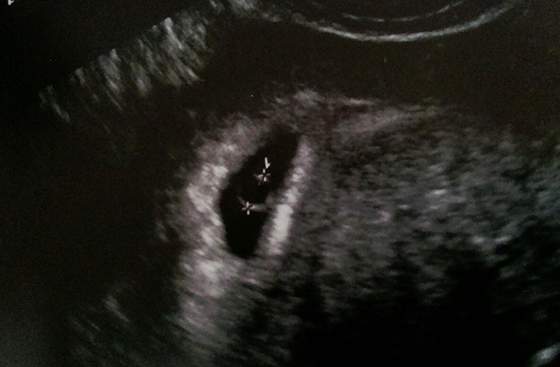

Kobietki pamietacie ta moja kumpelke co bala sie pustego jajeczka poraz drugi? Dzis byla u gina bo nie wytrzymala niepewnosci.

Oto efekt uploadfromtaptalk1434653613079.jpg

Jej z OM niby wychodzilo 6t5d wazne ze nie ma pustego jaja bo tego sie bala najbardziej bo juz raz miala.A wystraszyla sie bo lekarz jej powiedzial ze na 7 tydzien to nie wyglada tylko na 5...

To ja mam tak samo, tez jak bylam na usg to z om wychodzilo mi 6 tc i ktorys dzien, a z wymiarow usg ponad tydz mlodsza, a na usg mam pecherzyk ciazowy i w srodku pecherzyk zoltkowy, ale moze sie chyba okazac puste jesli zarodek nie powstanie i ja tego sie boje